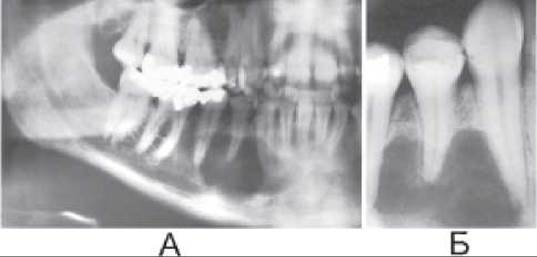

Мал. 312. Остеобластокластома на панорамній (А) та прицільній (Б) рентгенограмах.

Остеобластокластома (гігантоклітинна пухлина) має коміркову та літичну форми. Коміркова форма остеобластокластоми рентгенологічно визначається як ділянка здуття з доволі чіткими контурами та з тонкими перегородками, які утворюють різні за величиною комірки (мал. 312). Літична форма гігантоклітинної пухлини характеризується наявністю прояснення на рівні здуття, яке має неправильну овальну форму.